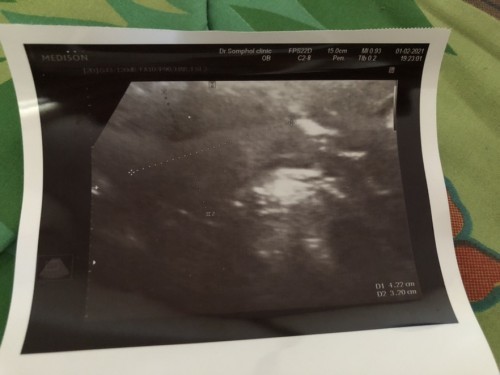

เมื่อวานวันที่ 1 ก.พ. เราได้ไปซาวด์ที่คลินิกมาค่ะหมอบอกว่าเราท้องนะคะเพราะเราตรวจเจอ2ขีดจางหลายอันมากแต่เรางงมากเลยค่ะทำไมถึงยังไม่เจอถุงตั้งครรภ์มีแม่ๆคนไหนเคยเป็นเราบ้างไหมคะ ( ประจำเดือนเรามาครั้งล่าสุดวันที่ 17 ธ.ค. 63 )